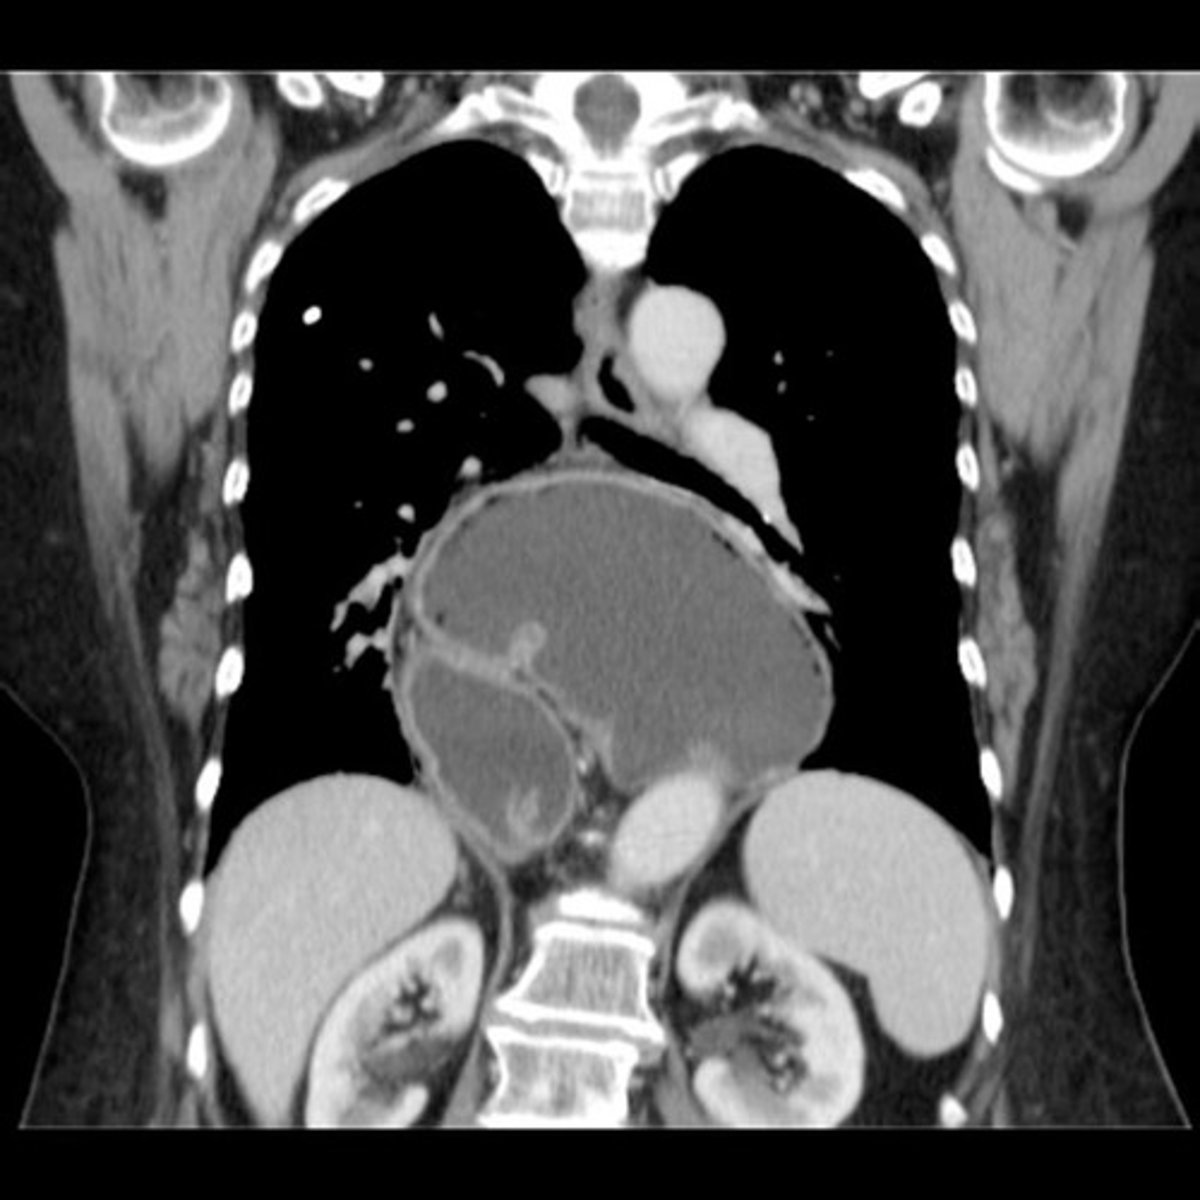

Abdominal aortic aneurysm on CT